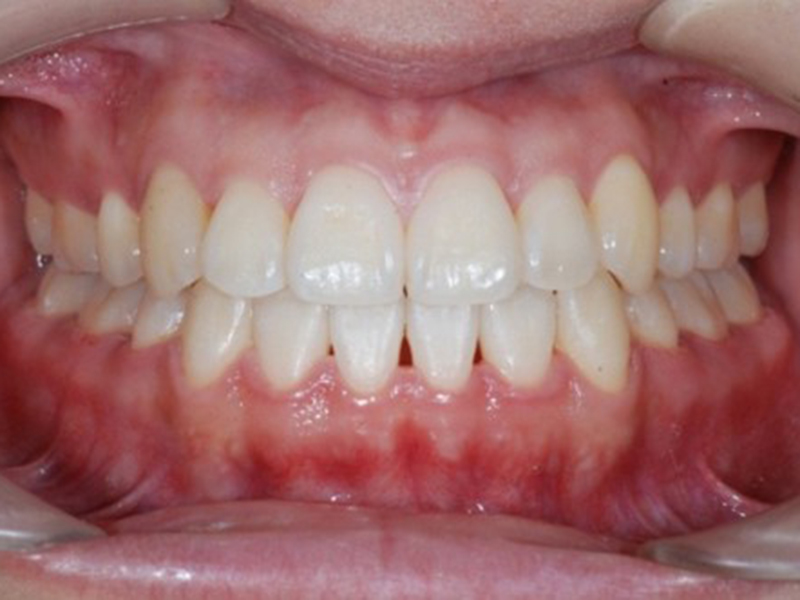

▼ ケース5 下顎前歯部叢生症例

治療終了時